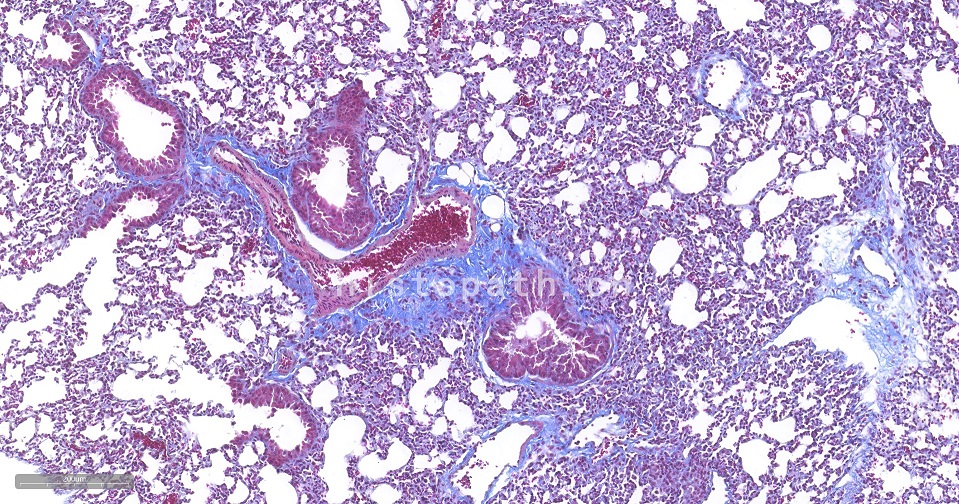

Masson染色原理:

Masson 三色染色又称马松染色,是结缔组织染色中最经典的一种方法,是胶原纤维染色权威而经典的技术方法。所谓三色染色通常是指染胞核和能选择性的显示胶原纤维和肌纤维。该法染色原理与阴离子染料分子的大小和组织的渗透有关:分子的大小由分子量来体现,小分子量易穿透结构致密、渗透性低的组织,而大分子量则只能进入结构疏松的、渗透性高的组织。然而,淡绿或苯胺蓝的分子量很大,因此 Masson 染色后肌纤维呈红色, 胶原纤维呈绿色或蓝色,主要用于区分胶原纤维和肌纤维。

染色结果:胶原纤维、黏液、软骨呈蓝色(如亮绿液染色为绿色),胞质、肌肉、纤维素、神经胶质呈红色,胞核黑蓝色。